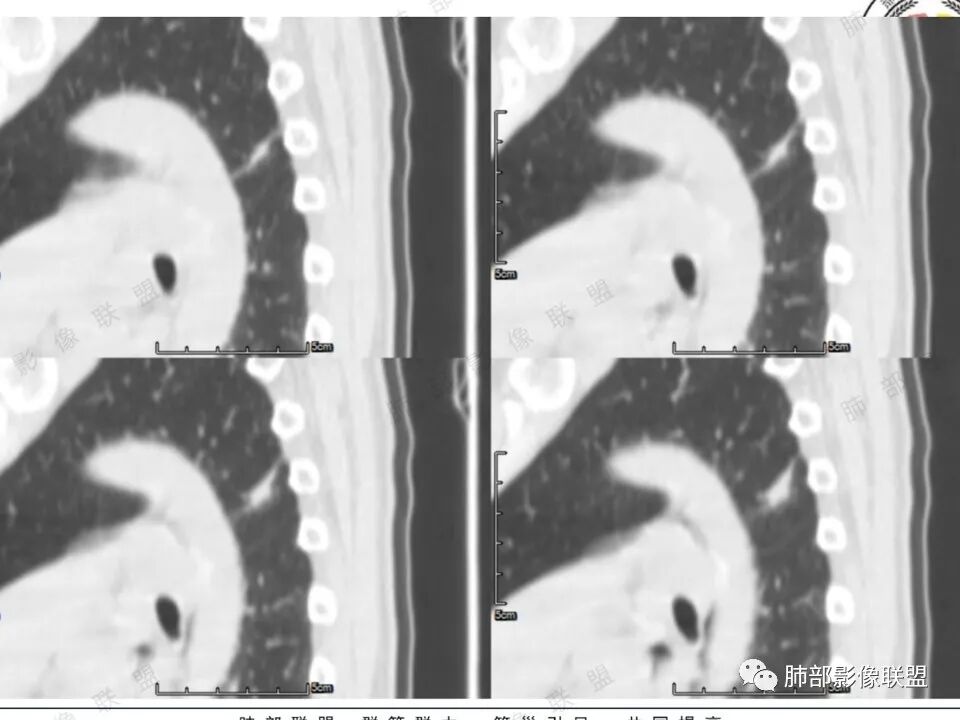

左肺上叶长条状病灶,胸膜牵拉,边缘平直,磨玻璃边界清楚,不均匀强化,考虑炎性,不完全排除肺癌

左肺上叶尖后段病灶,毛玻璃边界不清,实性成分边缘平直,重建,病灶长条形,增强明显强化,考虑炎症

中年女性,左肺上叶长条状病灶,宽基底与胸膜交界,胸膜凹陷,病灶边缘平直,局部收缩及膨隆,周围可见磨玻璃,其边界清楚,增强病灶不均匀强化,影像表现有炎性病变,也有明显占位表现,考虑OP,有膨胀性表现的小结节,不完全排除肺癌!需要结合相关检查。

患者中年女性,体检发现。胸部CT:左肺上叶后段长条形结节灶,边缘光滑,边界清楚,见分叶、毛刺、胸膜牵拉及平直征象。增强明显强化,内可见血管增粗,综合考虑恶性病变,浸润性腺癌可能大,鉴别结核。

左肺上叶后段条片状影,边缘部分模糊,前缘平直后缘澎隆,周围可见大部分清晰的GGO,毛刺不明显,可见索条影,内密度不均可见条状低密度,增强除条状低密度外明显强化。支气管似见病灶边缘截断。考虑腺癌可能,抗炎治疗除外炎性肉芽肿。